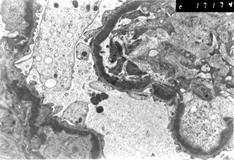

Рисунок. Болезнь плотных депозитов

Массивные электронноплотные депозиты комплемента СЗ в толще ГБМ.

При световой микроскопии характерен морфологический вариант МПГН, но нередко утолщение ГБМ не сопровождается наличием выраженной пролиферации и двойных контуров. При ЭМ картина кардинально отличается от таковой при МПГН I типа. В толще ГБМ отмечается наличие диффузных электронноплотных депозитов по типу шнуров. ГБМ становится толстой с черным центральным слоем (плотная пластинка). С течением болезни клубочки склерозируются. В тубулоинтерстициальном пространстве могут обнаруживаться атрофия канальцев, фиброз и воспалительные инфильтраты. В отдельных случаях также имеются экстракапиллярные полулуния.